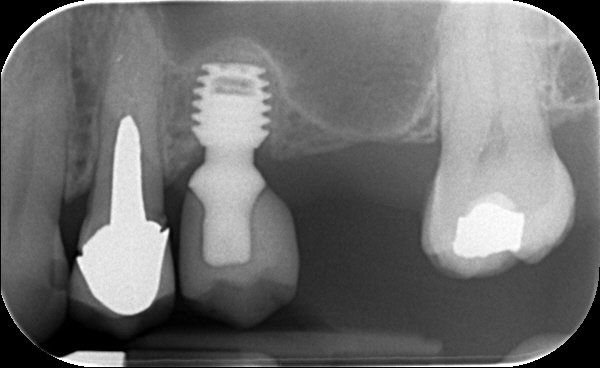

Before proceeding with implant treatment an examination is necessary to take impressions (to make models of your teeth) and take x-rays to assess your bone level and sometimes a cone beam (CBCT) scan especially if multiple implants are required. On the basis of this examination, a precise report, treatment plan and quotation is provided.

There are several types of restorations that can be used over an implant: